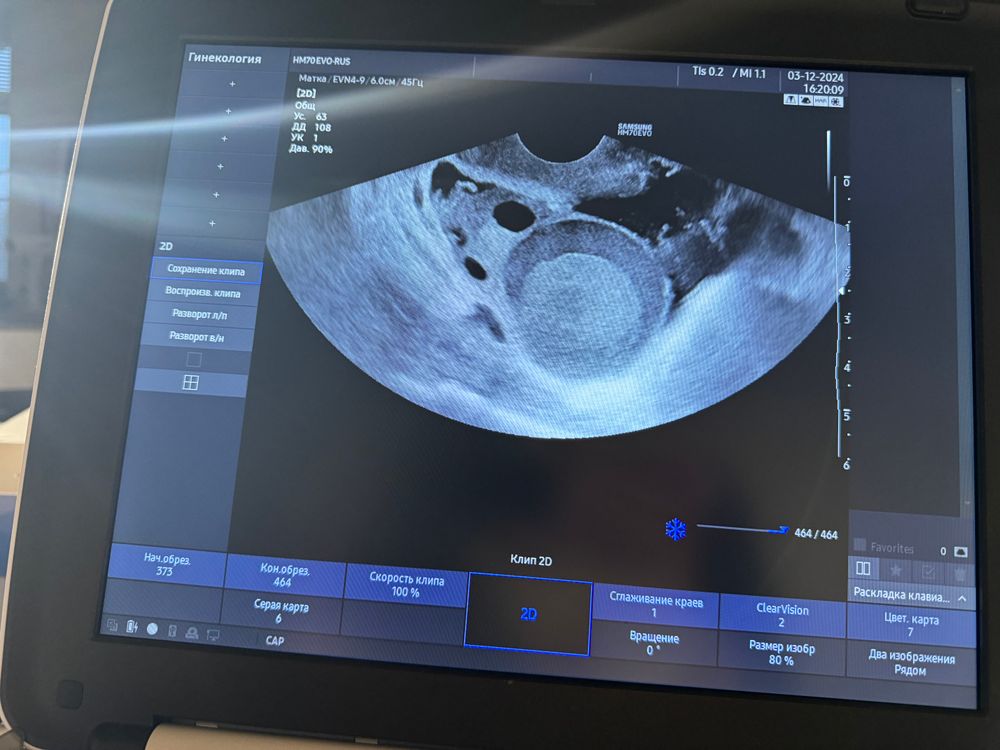

на сегодня у меня все не соответствует фазе цикла, в левом яичнике не понятное образование аж почти 4см, круглое и как будто киста в кисте, в правом не понятно тоже вроде как желтое тело ушло в кисту, оба яичника увеличены в размерах.

На фотке левый яичник с образованием